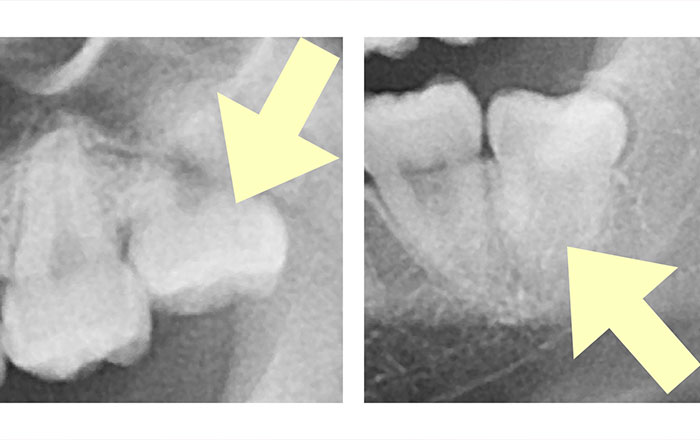

2.ななめ・真横に生えている親知らず

ななめや真横に生えている、上下の親知らずの抜歯の場合です。

難易度は普通〜難しいです。時間は30分〜90分ほどで、保険適用内だと治療費は4,000〜5,000円ほど、自由診療だと治療費は11,000円(税込)です。

親知らずを抜く時に気をつけなければいけない顎の神経を三叉神経と言い、特に下顎神経と言われるものが関わっています。

抜歯する時に神経を傷付けてはいけないので、神経との近さをレントゲンで調べますが、親知らずと神経との距離の近さにより、診査診断も異なります。